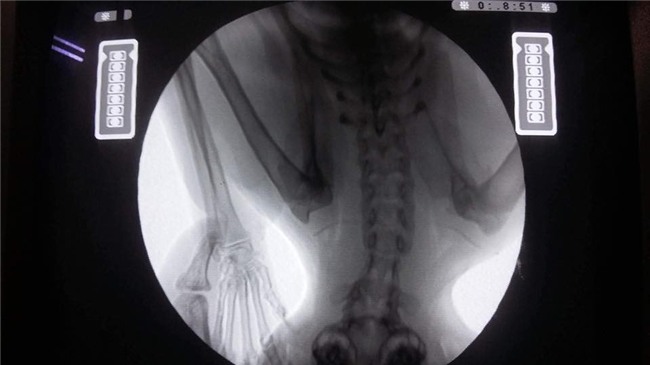

Bé mèo tên là Xù đang được nằm điều trị tại bệnh viện thú y IVET Lạc Long Quân. Bây giờ, bé đang bị liệt nửa người nên chỉ được truyền dịch và thông tiểu. Vì bị thương rất nặng nên bé phải nằm viện 2 đến 3 ngày nữa để hồi phục sức khỏe mới có thể phẫu thuật được.

May mắn là đã có một bệnh viện đồng ý chữa trị nhưng phải mời bác sỹ từ Thái Lan qua để giải phẫu. Chi phí cho 1 ngày điều tri tại viện là 1,4 triệu đồng và phải nằm khoảng 10 ngày. Chi phí mổ hàm của chú mèo là 2 triệu đồng trong khi phí phẫu thuật điều trị cột sống và thần kinh là 25 triệu đồng. Toàn bộ chi phí phẫu thuật và tiền viện phí lên đến hơn 40 triệu.